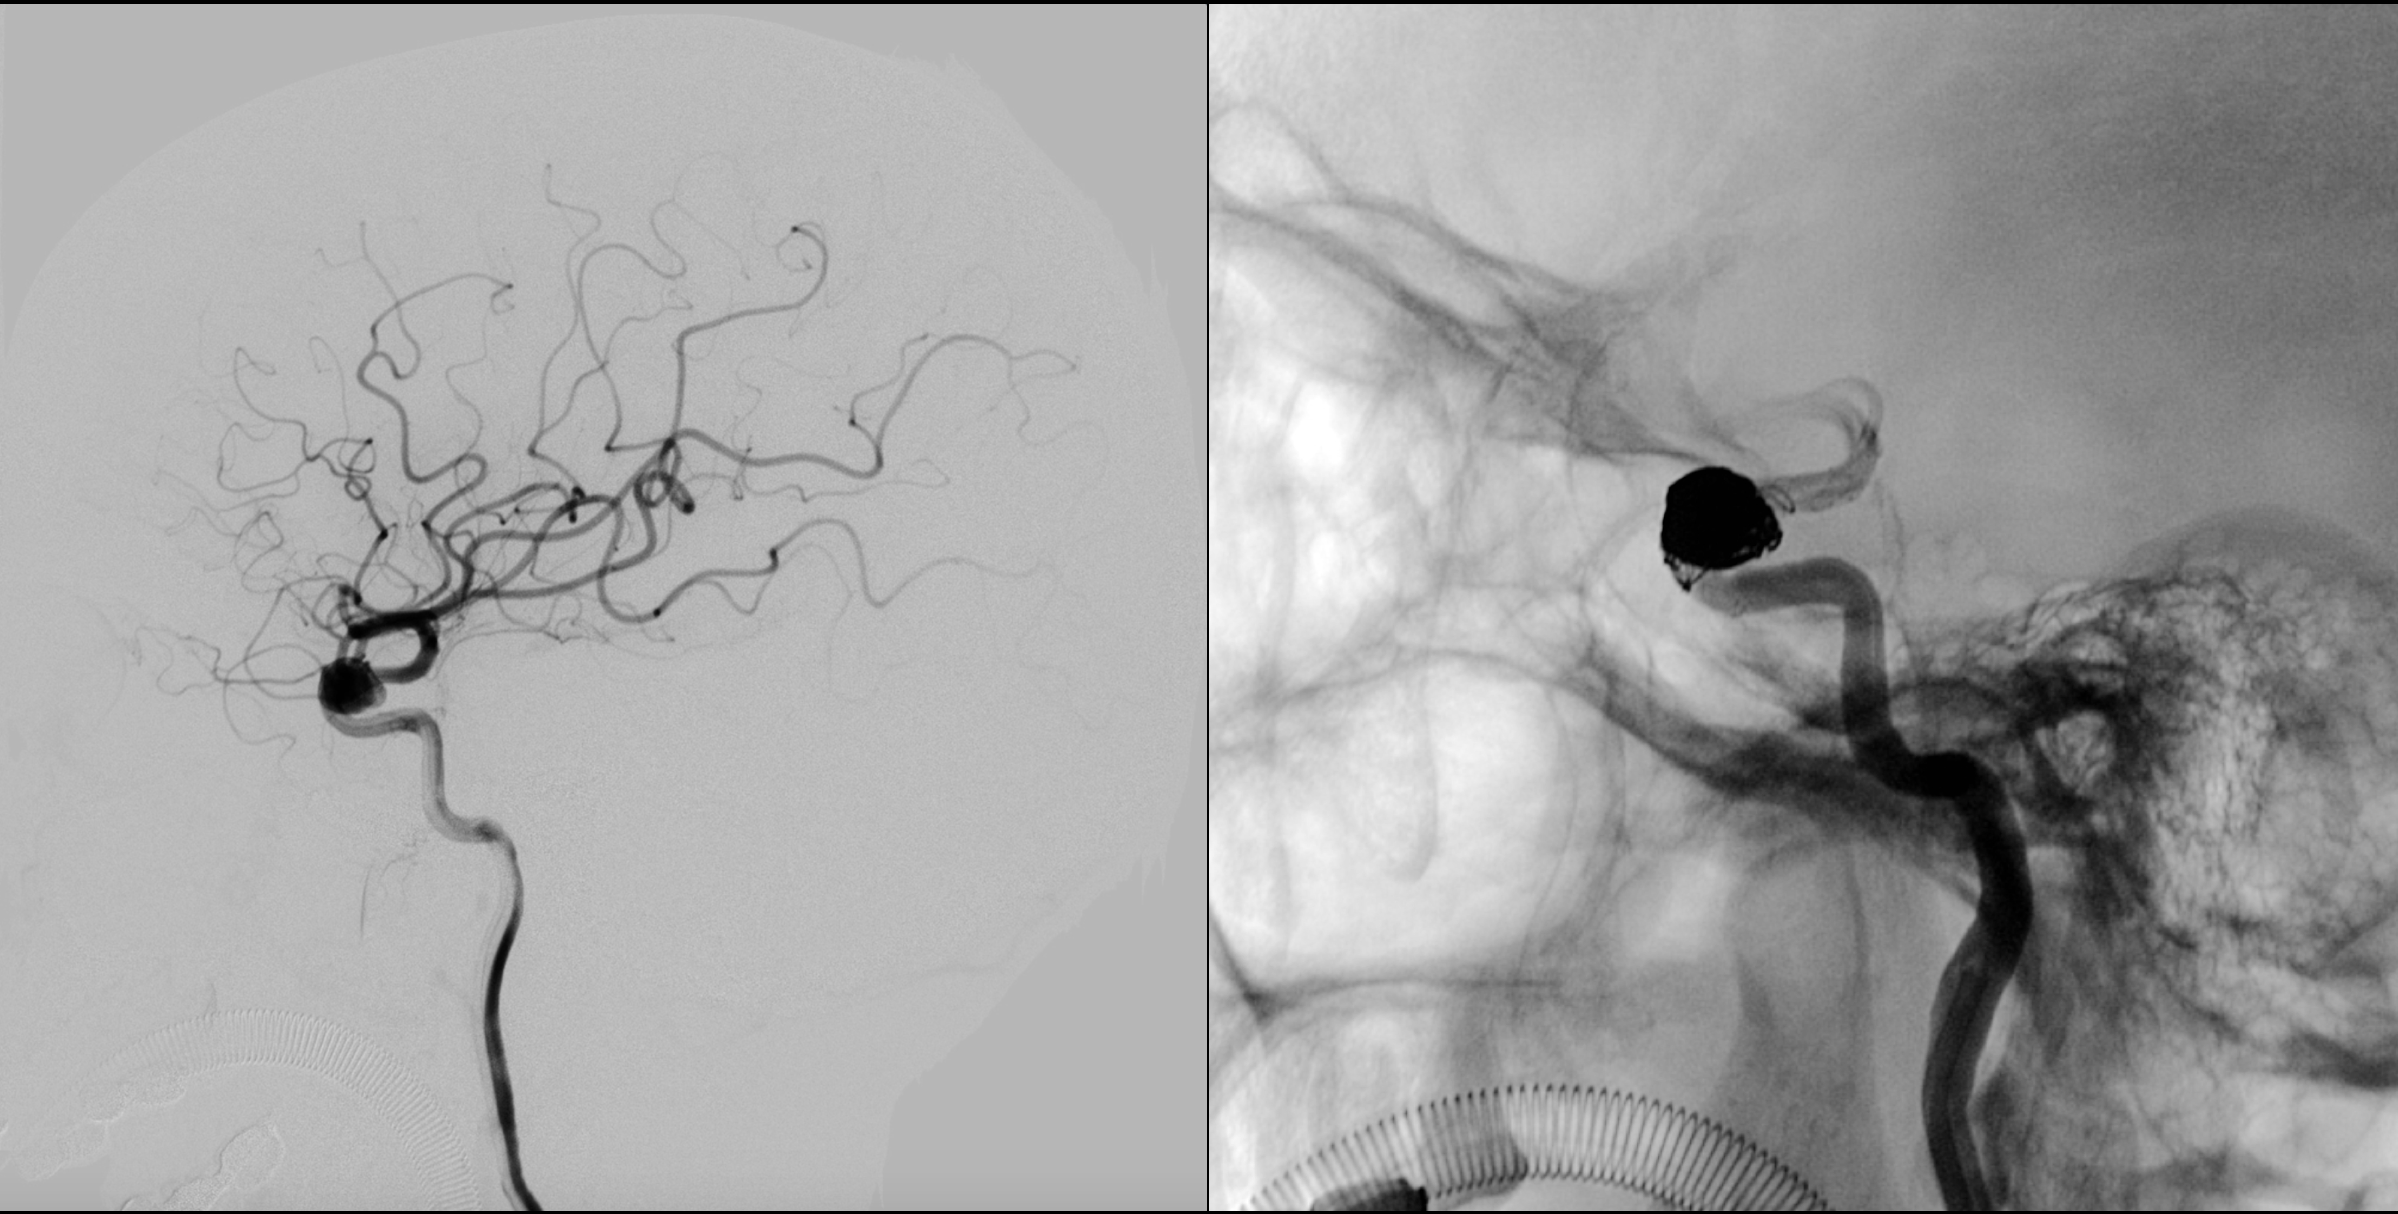

术后1年于2017年3月10日再次入院复查。右侧颈内动脉正位造影及蒙片显示:动脉瘤未见复发!

右侧颈内动脉侧位造影及蒙片显示:动脉瘤未见复发!

正侧位蒙片显示:支架及弹簧圈形态良好!

右侧颈内动脉三维重建:动脉瘤未见复发,载瘤动脉通畅!

右侧颈内动脉三维重建:动脉瘤未见复发,载瘤动脉通畅!